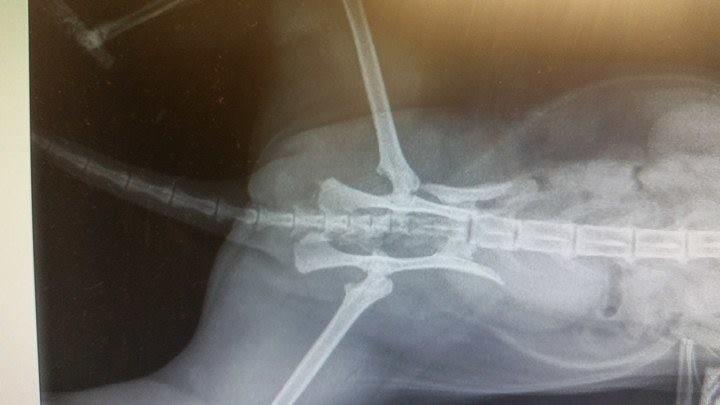

This evening, first working day of the week (Monday was Queen's Birthday weekend) I saw the surgeon. His name is David, and he put the x-rays up on screen again, and took me through the process of what would be done. She will have something called a 'string of pearls' which I visualise as a meccano piece with lots and lots of bolts. The bolts go into the bone, I guess they must be self-tapping. They hold the two slivers together.

He explained that so many days after the event (it will be nearly a week on Wednesday) all her muscles will have tightened and it will be very difficult to get the pelvis back to where it belongs; but he should at least be able to make a good job of widening the pelvis enough for faeces to go through it. See the x-ray attached, for what has happened. The pelvis has snapped off and shunted up forwards into the actual pelvis area.

He explained that the two bones, side by side as they are, would knit together and a big ball of bone would be created, encasing them. This big ball of bone would block most of the pelvic opening. So basically, had I chosen conservative care she would have been in for lifelong constipation, and a lifelong special diet, and lifelong complications that would involve lifelong care. He said the problem was that the pelvis generally would end up so small that when they needed to digitally investigate compacted colons (ick) for faeces they couldn't get their finger in the space because there isn't any; so what they end up doing is breaking the pelvis down the middle to try and make enough space.